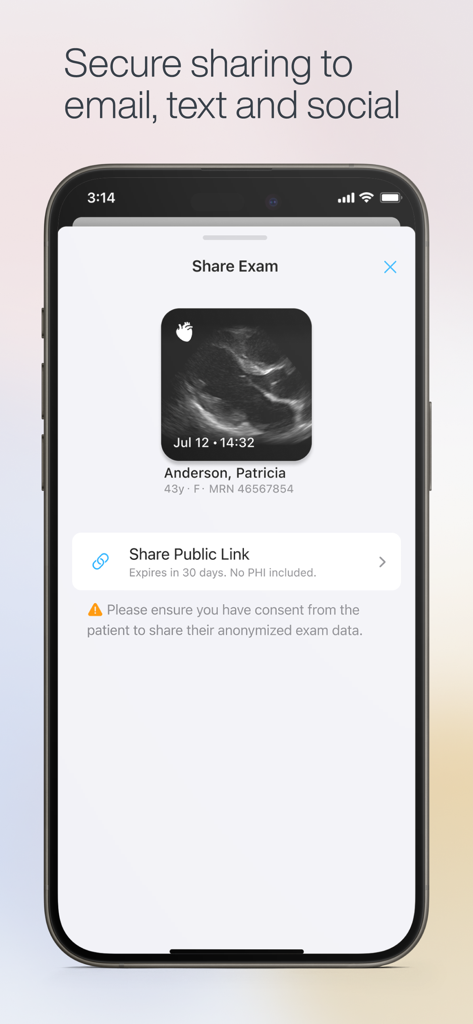

Exo Iris™ redefines the medical imaging ecosystem, blending high-performance proprietary silicon technology with real-time AI to deliver clinical answers when seconds count.

Versatile 3-in-1 Imaging

Perform cardiac, lung, and vascular scans with a single handheld device, eliminating the need for multiple probes and bulky hardware.

AI-Powered Clinical Insight

Achieve higher diagnostic confidence with real-time AI guidance that helps you capture the perfect window and automate complex measurements.